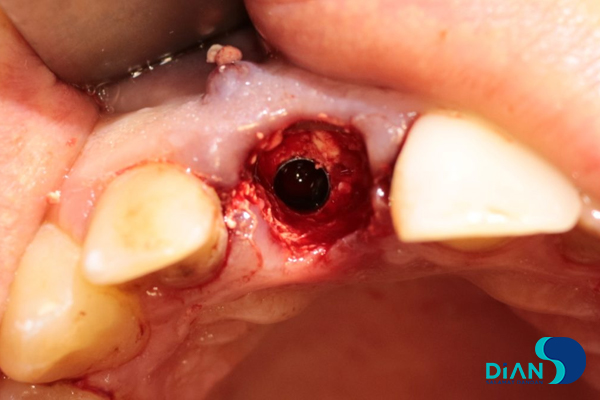

In the process of vestibular root fragment extraction the dentist found its interlocking with alveolar socket. There was a risk that a root fragment would break off with a part of alveolar socket. It was decided to apply «Socket shield» technique. The palatal root fragment was removed.

Then the dentist polished remained root part and conducted alveoli curettage.

The alveolar socket was washed with antiseptic solution, and then the dentist made osteotomy while considering the future correct position of dental implant in the socket in relation to 12, 21 and 31 teeth.